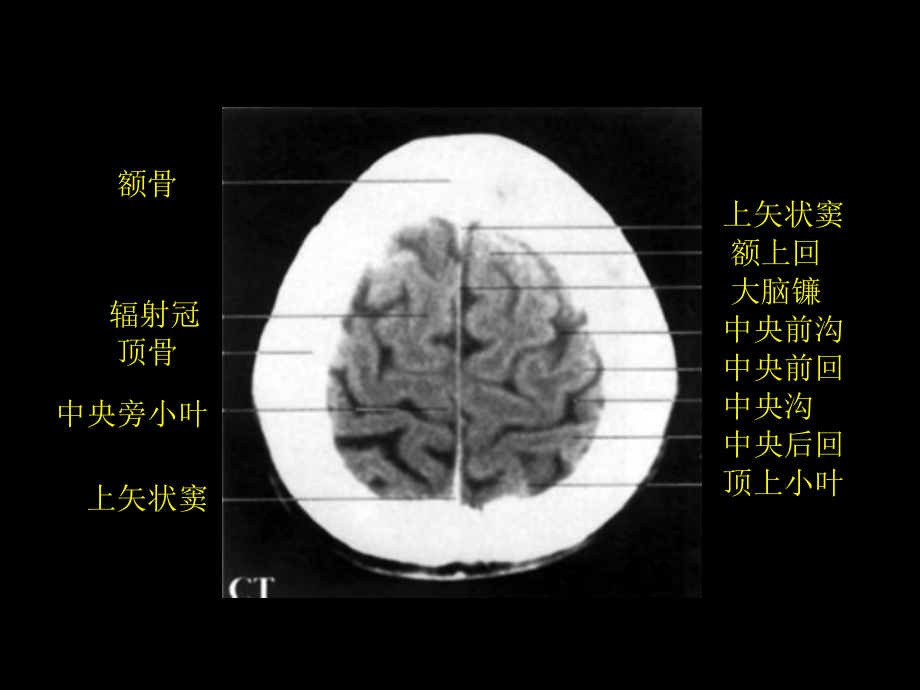

额骨辐射冠顶骨中央旁小叶上矢状窦上矢状窦额上回额上回大脑镰中央前沟中央前回中央沟中央后回顶上小叶额骨辐射冠顶骨中央旁小叶上矢状窦上矢状窦额上回中央前沟中央前回中央沟中央后回顶上小叶 额骨额上回辐射冠中央前回中央后回扣带沟缘支顶骨上矢状窦大脑镰额上回额中回中央前沟中央前回中央沟中央后回中央旁小叶顶上小叶额骨额上回额中回辐射冠顶骨中央前回中央沟中央后回扣带回缘支上矢状窦额上回额中回中央前沟中央前回中央沟中央后回中央旁小叶中央后沟顶上小叶上矢状窦额骨大脑镰(半卵园中心)辐射冠中央前回中央后回中央旁小叶顶骨楔前叶上矢状窦上矢状窦额上回额中回中央前回中央沟中央后回缘上回角回顶上小叶额上回额中回中央前回辐射冠中央旁小叶楔前叶上矢状窦额上回额中回中央前回中央沟中央后回缘上回顶上小叶上矢状窦额骨大脑镰中央前回中央沟中央后回辐射冠顶骨上矢状窦上矢状窦额上回额中回额下回中央前沟中央前回中央沟中央后回缘上回楔前回楔叶额上回额中回额下回中央前回辐射冠楔前叶额上回额中回额下回中央前回中央后回中央后沟缘上回角回上矢状窦额上回额中回扣带沟扣带回额下回中央前回中央沟中央后回缘上回角回楔叶大脑镰额中回额下回辐射冠尾状核体透明隔侧脑室中央部胼胝体下矢状窦扣带回楔前叶大脑镰上矢状窦额上回扣带沟胼胝体辐射冠尾状核体透明隔下矢状窦扣带回扣带沟顶枕沟上矢状窦额上回额中回扣带回额下回中央前回尾状核体中央后回侧脑室中央部缘上回角回楔前叶楔叶额上回额中回额下回胼胝体膝尾状核头岛叶背侧丘脑穹窿体侧脑室后脚扣带回大脑镰上矢状窦上矢状窦扣带回侧脑室前脚中央前回壳中央后回内囊后肢胼胝体压部大脑大静脉直窦楔前叶楔叶扣带回侧脑室前脚尾状核头透明隔穹窿体背侧丘脑侧脑室后脚大脑大静脉直窦楔前叶顶枕沟上矢状窦额上回额中回额下回胼胝体膝部中央前回壳中央后回岛叶胼胝体压部缘上回扣带回角回楔叶额骨扣带回侧脑室前脚尾状核头壳穹窿柱第三脑室内囊后肢松果体大脑内静脉直窦上矢状窦额上回额中回额下回胼胝体膝部大脑外侧窝池透明隔苍白球背侧丘脑听辐射尾状核尾侧脑室三角视辐射楔叶扣带回侧脑室前脚壳穹窿柱第三脑室内囊后肢背侧丘脑胼胝体压部侧脑室后脚上矢状窦额上回额中回额下回胼胝体膝部大脑外侧窝池尾状核头岛叶颞横回颞上回听辐射颞中回直窦视辐射颞下回楔叶额窦额下回大脑外侧窝池第三脑室中脑水管四叠体池小脑蚓额上回额中回额下回大脑外侧窝池颞上回大脑脚底红核下丘小脑幕额窦颞肌隔区尾状核头前连合中脑水管下丘海马旁回直窦上矢状窦额上回额中回额下回大脑外侧窝池壳颞上回第三脑室大脑脚底四叠体池侧脑室下脚小脑蚓枕颞内侧回枕颞外侧回额窦颞肌鞍上池桥池横窦窦汇眶腔直回颞上回颞中回后床突桥脑基底部第四脑室小脑蚓小脑半球上睑板泪腺蝶骨大翼颞肌颞上回杏仁体侧脑室下角海马颞中回枕颞内侧回枕颞内侧回枕颞外侧回额窦眼球鸡冠眶脂体视神经直回颞上回眶回视交叉漏斗鞍上池桥脑基底部颞中回第四脑室小脑蚓小脑半球横窦直窦窦汇鼻中隔中筛窦后筛窦颞肌基底动脉横窦小脑半球枕内隆凸晶体眼球内直肌外直肌视神经颞中回颞肌脑桥基底部第四脑室小脑蚓枕窦鼻中隔中筛窦颞肌颞中回桥脑海马旁回颞下回横窦枕骨晶体眼球外直肌内直肌视神经后筛窦颞中回垂体基底动脉颞下回脑桥基底部脑桥被盖部第四脑室小脑蚓小脑半球枕内隆凸眼球鼻腔颞肌颞下回脑桥小脑三角池鼓室小脑半球枕内隆凸眶腔蝶窦颞骨岩部脑桥第四脑室小脑蚓鼻腔眶脂体筛窦颞肌颞下回基底动脉脑桥第四脑室枕内隆凸鼻中隔筛泡中鼻甲颞肌蝶窦颞下回颈内动脉三叉神经颞骨岩部延髓小脑蚓小脑半球枕窦上颌窦颧弓咬肌翼腭窝关节结节下颌头外耳道颈内静脉乳突小房头半棘肌鼻中隔下鼻甲冠突颞肌梨骨翼外肌枕骨基底部颈内动脉舌下神经管延髓小脑半球头夹肌上颌窦颧弓咬肌翼外肌延髓头半棘肌鼻中隔下鼻甲上颌窦冠突颞肌梨骨枕骨基底部下颌头乙状窦小脑半球枕内隆凸大脑镰辐射冠上睑提肌及上直肌额窦眼球中鼻甲中鼻道上颌窦颊肌额上回额中回眶回直回外直肌内直肌下直肌鼻中隔下鼻甲颊肌上矢状窦辐射冠扣带回直回上斜肌外直肌中鼻道鼻中隔颊肌额上回额中回额下回上睑提肌及上直肌内直肌视神经下直肌中鼻甲上颌窦下鼻甲舌颊肌上矢状窦辐射冠扣带回直回内直肌视神经与外直肌下直肌中鼻甲鼻中隔下鼻甲颊肌舌下腺下颌骨额上回额中回额下回眶回上睑提肌及上直肌上斜肌筛窦颞肌颧弓上颌窦咬肌舌颊脂体颏舌肌颏舌骨肌额骨辐射冠扣带回胼胝体膝部外侧沟颞极蝶窦颧弓下鼻甲上颌窦硬腭及腭腺下颌骨咬肌上矢状窦额上回额中回额下回侧脑室前角颞肌直回视神经眼动静脉颞极筛窦鼻中隔下颌骨冠突舌颏舌肌舌下腺额上回额中回辐射冠胼胝体透明隔大脑外侧窝池岛叶直回蝶窦鼻腔翼内肌咬肌上矢状窦额上回额中回扣带回额下回尾状核头壳终板旁回动眼神经颞叶颞肌翼外肌翼内肌舌肌额骨辐射冠扣带回侧脑室中央部透明隔隔核伏隔核视交叉漏斗垂体颞肌蝶窦咽鼓管咽口咽腔咬肌舌神经上矢状窦额上回额中回中央前回胼胝体尾状核头壳岛叶颞上回颈内动脉颞下回翼外肌翼内肌咬肌额上回扣带回侧脑室中央部透明隔壳背侧丘脑海马基底动脉下颌头腮腺咽腔咬肌上矢状窦额上回中央前回大脑前动脉中央后回胼胝体干尾状核体室间孔壳第三脑室大脑后动脉侧脑室下角海马旁回颈内动脉翼外肌腮腺下颌骨翼内肌中央旁小叶中央后回辐射冠扣带回侧脑室中央部穹窿体背侧丘脑壳脑桥三叉神经根枕骨基底部腮腺颈内静脉上矢状窦中央前回中央后回顶上小叶胼胝体干尾状核体内囊前肢第三脑室颞上回中脑颞中回海马旁回枕颞外侧回颈内静脉腮腺中央旁小叶辐射冠扣带回侧脑室中央部颞上回背侧丘脑环池海马旁回小脑中脚脑桥小脑三角池腮腺上矢状窦中央前回中央后回顶上小叶缘上回胼胝体干第三脑室大脑脚侧脑室下角颞下回枕颞内侧回延髓腮腺齿突颈内静脉上矢状窦中央旁小叶辐射冠扣带回胼胝体压部上丘下丘小脑上脚小脑中脚小脑半球延髓椎动脉头下斜肌中央后回顶上小叶缘上回侧脑室三角颞上回松果体侧脑室下角颞中回颞下回第四脑室乙状窦脊髓中央旁小叶辐射冠扣带回距状沟小脑蚓小脑延髓池胸锁乳突肌头后大直肌头下斜肌头半棘肌上矢状窦中央后回顶上小叶缘上回颞上回侧脑室后角颞中回颞下回枕颞内侧回小脑半球小脑扁桃体头上斜肌头后大直肌头半棘肌头颊肌楔前叶辐射冠楔叶禽距直窦枕颞外侧回横窦头后大直肌头颊肌头半棘肌上矢状窦顶上小叶角回侧脑室后角距状沟枕颞内侧回小脑蚓小脑半球小脑延髓池头后小直肌头夹肌头下斜肌楔前叶辐射冠距状沟枕颞内侧回横窦头后大直肌头半棘肌上矢状窦顶上小叶枕上回楔叶侧脑室后角直窦枕颞外侧回小脑半球头后小直肌头夹肌距状沟辐射冠枕颞外侧回横窦头半棘肌上矢状窦楔叶舌回枕颞内侧回直窦小脑半球头夹肌楔叶舌回枕颞内侧回枕颞外侧回上矢状窦大脑镰枕外侧回上矢状窦中央前回中央沟额下回外侧沟颞上回颞中回颞肌髁突腮腺咬肌中央后回缘上回角回颞下回外耳道乳突小房胸锁乳突肌颈外静脉中央前回中央沟额中回辐射冠额下回外侧沟颞上回颞中回颞肌髁突上颌窦翼内肌中央后回顶上小叶缘上回角回横窦小脑半球乙状窦翼外肌头夹肌腮腺胸锁乳突肌中央前回中央沟额中回额骨岛叶额极上睑提肌及上直肌眶脂体颞极上颌窦翼外肌翼内肌下颌下腺中央后回顶上小叶缘上回辐射冠角回枕叶横窦侧脑室下角小脑半球乙状窦头上斜肌头夹肌颈内静脉头半棘肌斜方肌中央前回中央前沟额中回辐射冠壳眶回外侧沟与大脑中动脉颞极上颌窦翼外肌翼内肌颈内动脉中央后回中央沟顶上小叶楔叶侧脑室三角侧脑室下角横窦小脑半球颈内动脉乙状窦椎动、静脉颈内静脉 头下斜肌头半棘肌头夹肌中央前回中央沟额上回辐射冠内囊后肢尾状核头背侧丘脑额窦杏仁体筛窦颈内动脉下鼻甲口咽舌下腺中央后回楔前叶顶枕沟楔叶侧脑室距状沟横窦小脑半球三叉神经根脑桥小脑三角池乙状窦头后大直肌头半棘肌头下斜肌头夹肌中央前回额上回扣带沟扣带回侧脑室背侧丘脑视束大脑脚垂体蝶窦中鼻甲鼻咽下鼻甲椎间盘颏舌肌会咽中央沟中央后回楔前叶楔叶顶枕沟胼胝体压部距状沟舌回横窦脑桥小脑半球斜坡头后大直肌头半棘肌头夹肌中央前沟中央前回额上回扣带沟扣带回侧脑室背侧丘脑室间孔第三脑室乳头体视交叉垂体蝶窦上鼻甲延髓鼻咽舌口咽舌下腺中央沟中央后回扣带沟缘支楔前叶顶枕沟楔叶穹窿体距状沟四叠体池中脑水管小脑第四脑室桥池小脑延髓池小脑扁桃体头半棘肌寰椎前弓脊髓中央前回额上回扣带沟扣带回胼胝体尾状核体背侧丘脑视束桥池筛窦蝶窦下鼻甲舌舌下腺中央沟中央后回扣带沟缘支楔前叶顶枕沟侧脑室楔叶丘脑枕舌回大脑脚脑桥小脑半球小脑扁桃体头后大直肌头半棘肌头夹肌中央前沟中央前回中央沟额上回辐射冠内囊后肢壳额窦杏仁体海马旁回眼球颈内动脉上颌窦翼外肌翼内肌下牙槽神经顶骨中央后回中央后沟顶上小叶顶枕沟楔叶侧脑室三角背侧丘脑距状沟舌回横窦小脑半球三叉神经根脑桥小脑三角池头后大直肌横突孔与椎动脉头半棘肌头下斜肌颈长肌头夹肌中央前回中央前沟额中回辐射冠上睑提肌与上直肌角膜颞极下直肌蝶骨大翼翼外肌上颌窦翼内肌茎突咽肌二腹肌与茎突舌骨肌下颌下腺中央后回中央沟顶上小叶壳岛叶侧脑室下角枕叶横窦小脑半球乙状窦头半棘肌头下斜肌头夹肌颈内动脉斜方肌中央前回中央前沟额中回辐射冠岛叶额下回外侧沟颞叶颞肌翼外肌上颌窦茎突与茎突舌肌茎突咽肌茎突舌骨肌中央后回中央沟中央后沟角回辐射冠枕叶横窦小脑半球鼓室头上斜肌头夹肌头半棘肌颈内静脉中央前回中央沟额中回辐射冠额下回外侧沟颞上回颞肌关节结节下颌骨髁突翼外肌下颌骨咬肌中央后回缘上回角回颞横回枕叶横窦小脑半球外耳道头夹肌腮腺中央沟中央前回额下回外侧沟颞上回颞中回颞肌颧弓咬肌中央后回缘上回颞下回乳突小房下颌骨髁突外耳道腮腺额叶前内侧支中央前沟动脉大脑中动脉中央沟动脉颈内动脉中央后沟动脉大脑后动脉角回动脉直窦上矢状窦大脑前动脉中央前沟动脉大脑前动脉中央沟动脉后交通动脉基底动脉小脑上动脉角回动脉顶枕动脉距状沟动脉横窦大脑上静脉大脑前动脉大脑后动脉颈内动脉基底动脉颈内动脉颈外动脉颈内动脉上矢状窦额叶前内侧支中央前沟动脉大脑中动脉乙状窦横窦椎动脉椎动脉颈内静脉额叶后内侧支额叶中内侧支额叶前内侧支大脑前动脉大脑中动脉大脑后动脉基底动脉颈内动脉颈外动脉上矢状窦大脑上静脉旁中央动脉楔前动脉大脑大静脉直窦横窦乙状窦颈内静脉椎动脉。